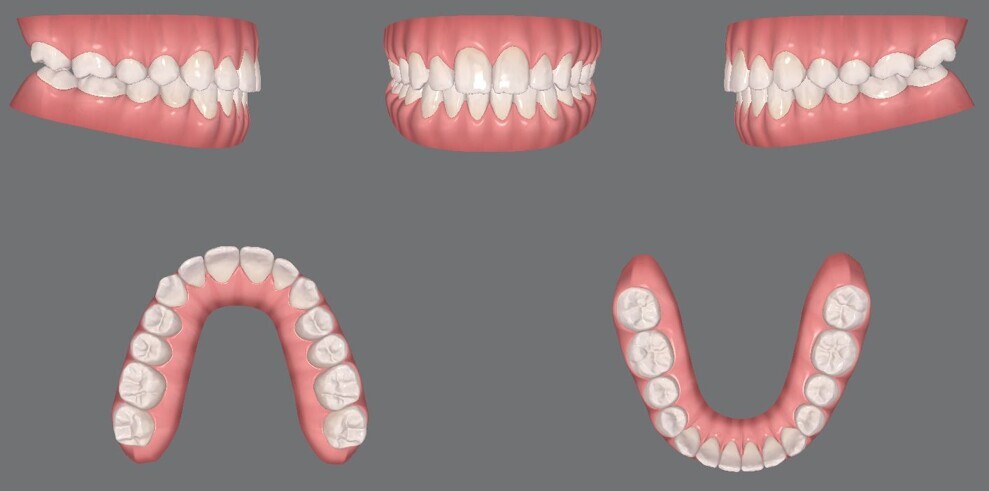

Figs. 12a–e: Pre-aligner treatment digital models

Figs. 14a–e: Mid-treatment digital models.

Figs. 24a–e: Final digital models.